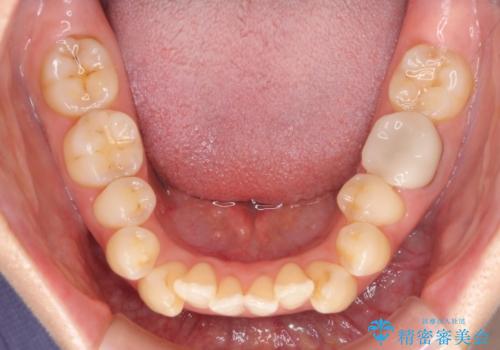

上顎左右第一小臼歯2本、下顎左右第二小臼歯2本を抜歯し、ワイヤー装置にて口元を引っ込めるよう矯正治療を行うこととしました。

上下の前歯に隙間が空くほど上顎前歯が前に飛び出していましたが、抜歯矯正により上下前歯がぴったりと付くほど口元を引っ込めることができました。